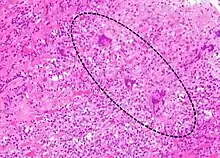

| A microscope image of myocarditis at autopsy in a person with acute onset of heart failure | |

Most forms of myocarditis involve the infiltration of heart tissues by one or two types of pro-inflammatory blood cells, lymphocytes and macrophages plus two respective descendants of these cells, NK cells and macrophages. Eosinophilic myocarditis is a subtype of myocarditis in which cardiac tissue is infiltrated by another type of pro-inflammatory blood cell, the eosinophil. Eosinophilic myocarditis is further distinguished from non-eosinophilic myocarditis by having a different set of causes and recommended treatments.[34][18]

The gold standard is the biopsy of the myocardium, in general done in the setting of angiography. A small tissue sample of the endocardium and myocardium is taken and investigated. The cause of the myocarditis can be only identified by a biopsy. Endomyocardial biopsy samples are assessed for histopathology (how the tissue looks like under the microscope): myocardial interstitium may show abundant edema and inflammatory infiltrate, rich in lymphocytes and macrophages. Focal destruction of myocytes explains the myocardial pump failure.[10] In addition samples may be assessed with immunohistochemistry to determine which types of immune cells are involved in the reaction and how they are distributed. Furthermore, PCR and/or RT-PCR may be performed to identify particular viruses. Finally, further diagnostic methods like microRNA assays and gene-expression profile may be performed.